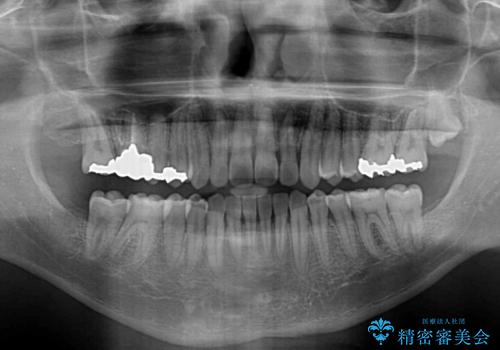

- 咬み合わせにより上顎正中に隙間ができているとのことで来院された患者様です。

インビザラインは自己管理が煩わしく、表側のワイヤー装置は目立つので避けたいとのことで、上顎だけが裏側装置のハーフリンガルにて矯正治療を行うこととしました。

矯正治療中に結婚式があったそうですが、隙間も改善しており、一部装置を外すことなく挙式できたとのことでした。